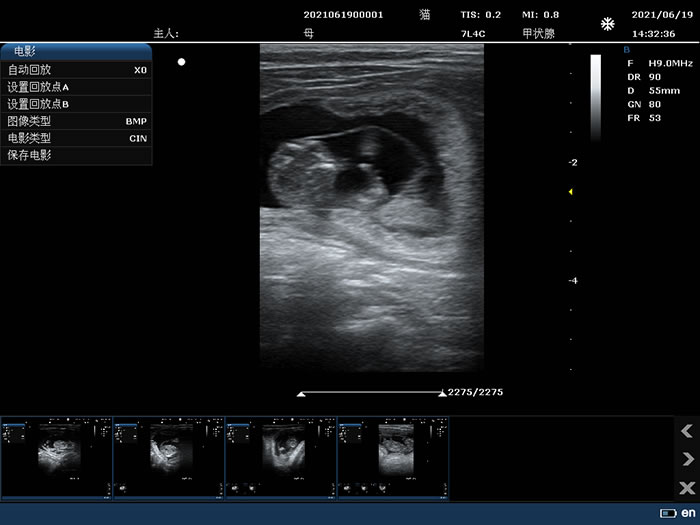

7L4C: 7.5MHz/L38mm/128阵元线阵探头;

2.10 电影回放

2D模式,B最大: ≥5000帧,Color, PDI最大:≥2300帧;

支持JPG、BMP、FRM图像格式和CIN、AVI电影格式(AVI视频压缩倍率≥30);